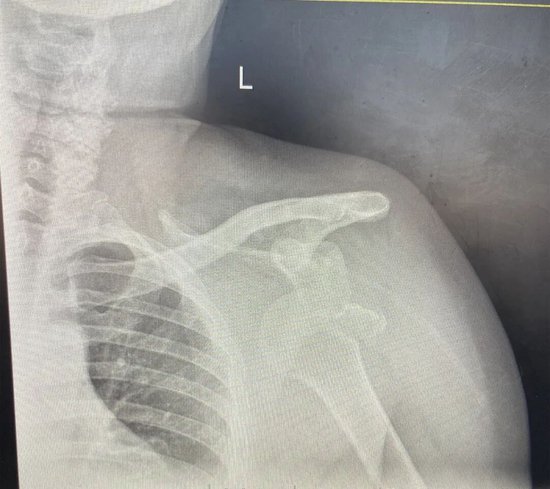

这位57岁的法国患者因“外伤致左肩部疼痛6天”来院就诊。经左肩DR检查,王帅诊断为“左肩关节脱位伴左肱骨大结节骨折”。由于伤后近一周才就医,患者肱骨头呈前下脱位且骨折部位已被关节盂下缘嵌顿,左上臂中度肿胀,这些都大大增加了手法复位的难度与风险。

在患者放松后,王帅采用持续手法牵引结合足蹬法进行复位。他操作轻柔、稳健,最大限度避免了对骨折块及周围神经血管的附加损伤。复查DR显示:左肩关节复位成功,骨折处对位对线良好。

(复位前DR结果)